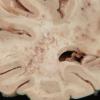

INFECTION

PML (JC Virus)

PML - Gross Pathology (2)